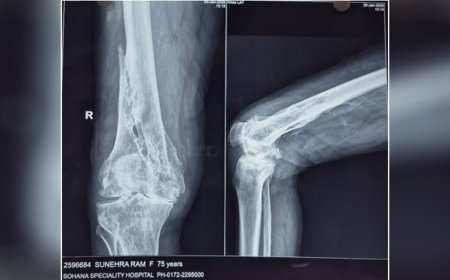

The case involved a 75-year-old male patient suffering from severe post-traumati...